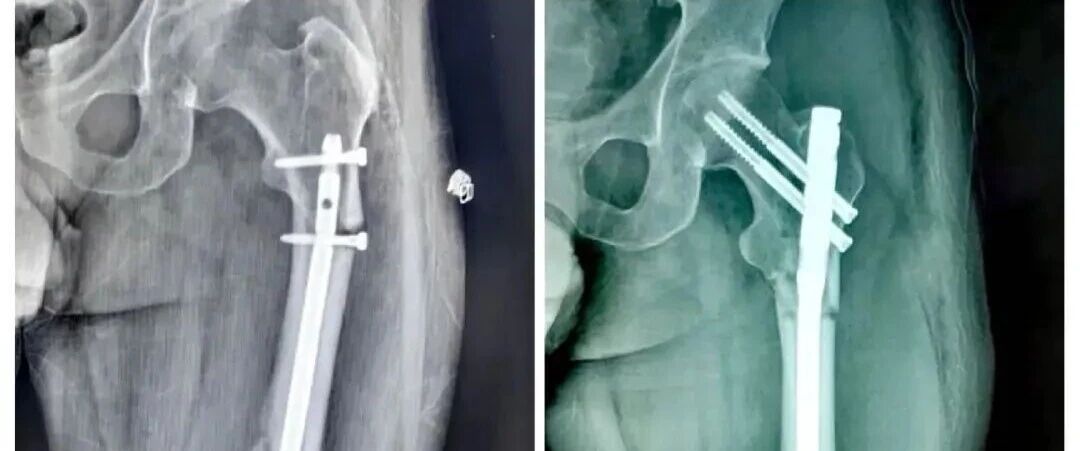

呼盆唤友 骨盆骨折手术专题课程

244分钟

3.8万人学习

人工髋膝关节置换术流程化管理

160分钟